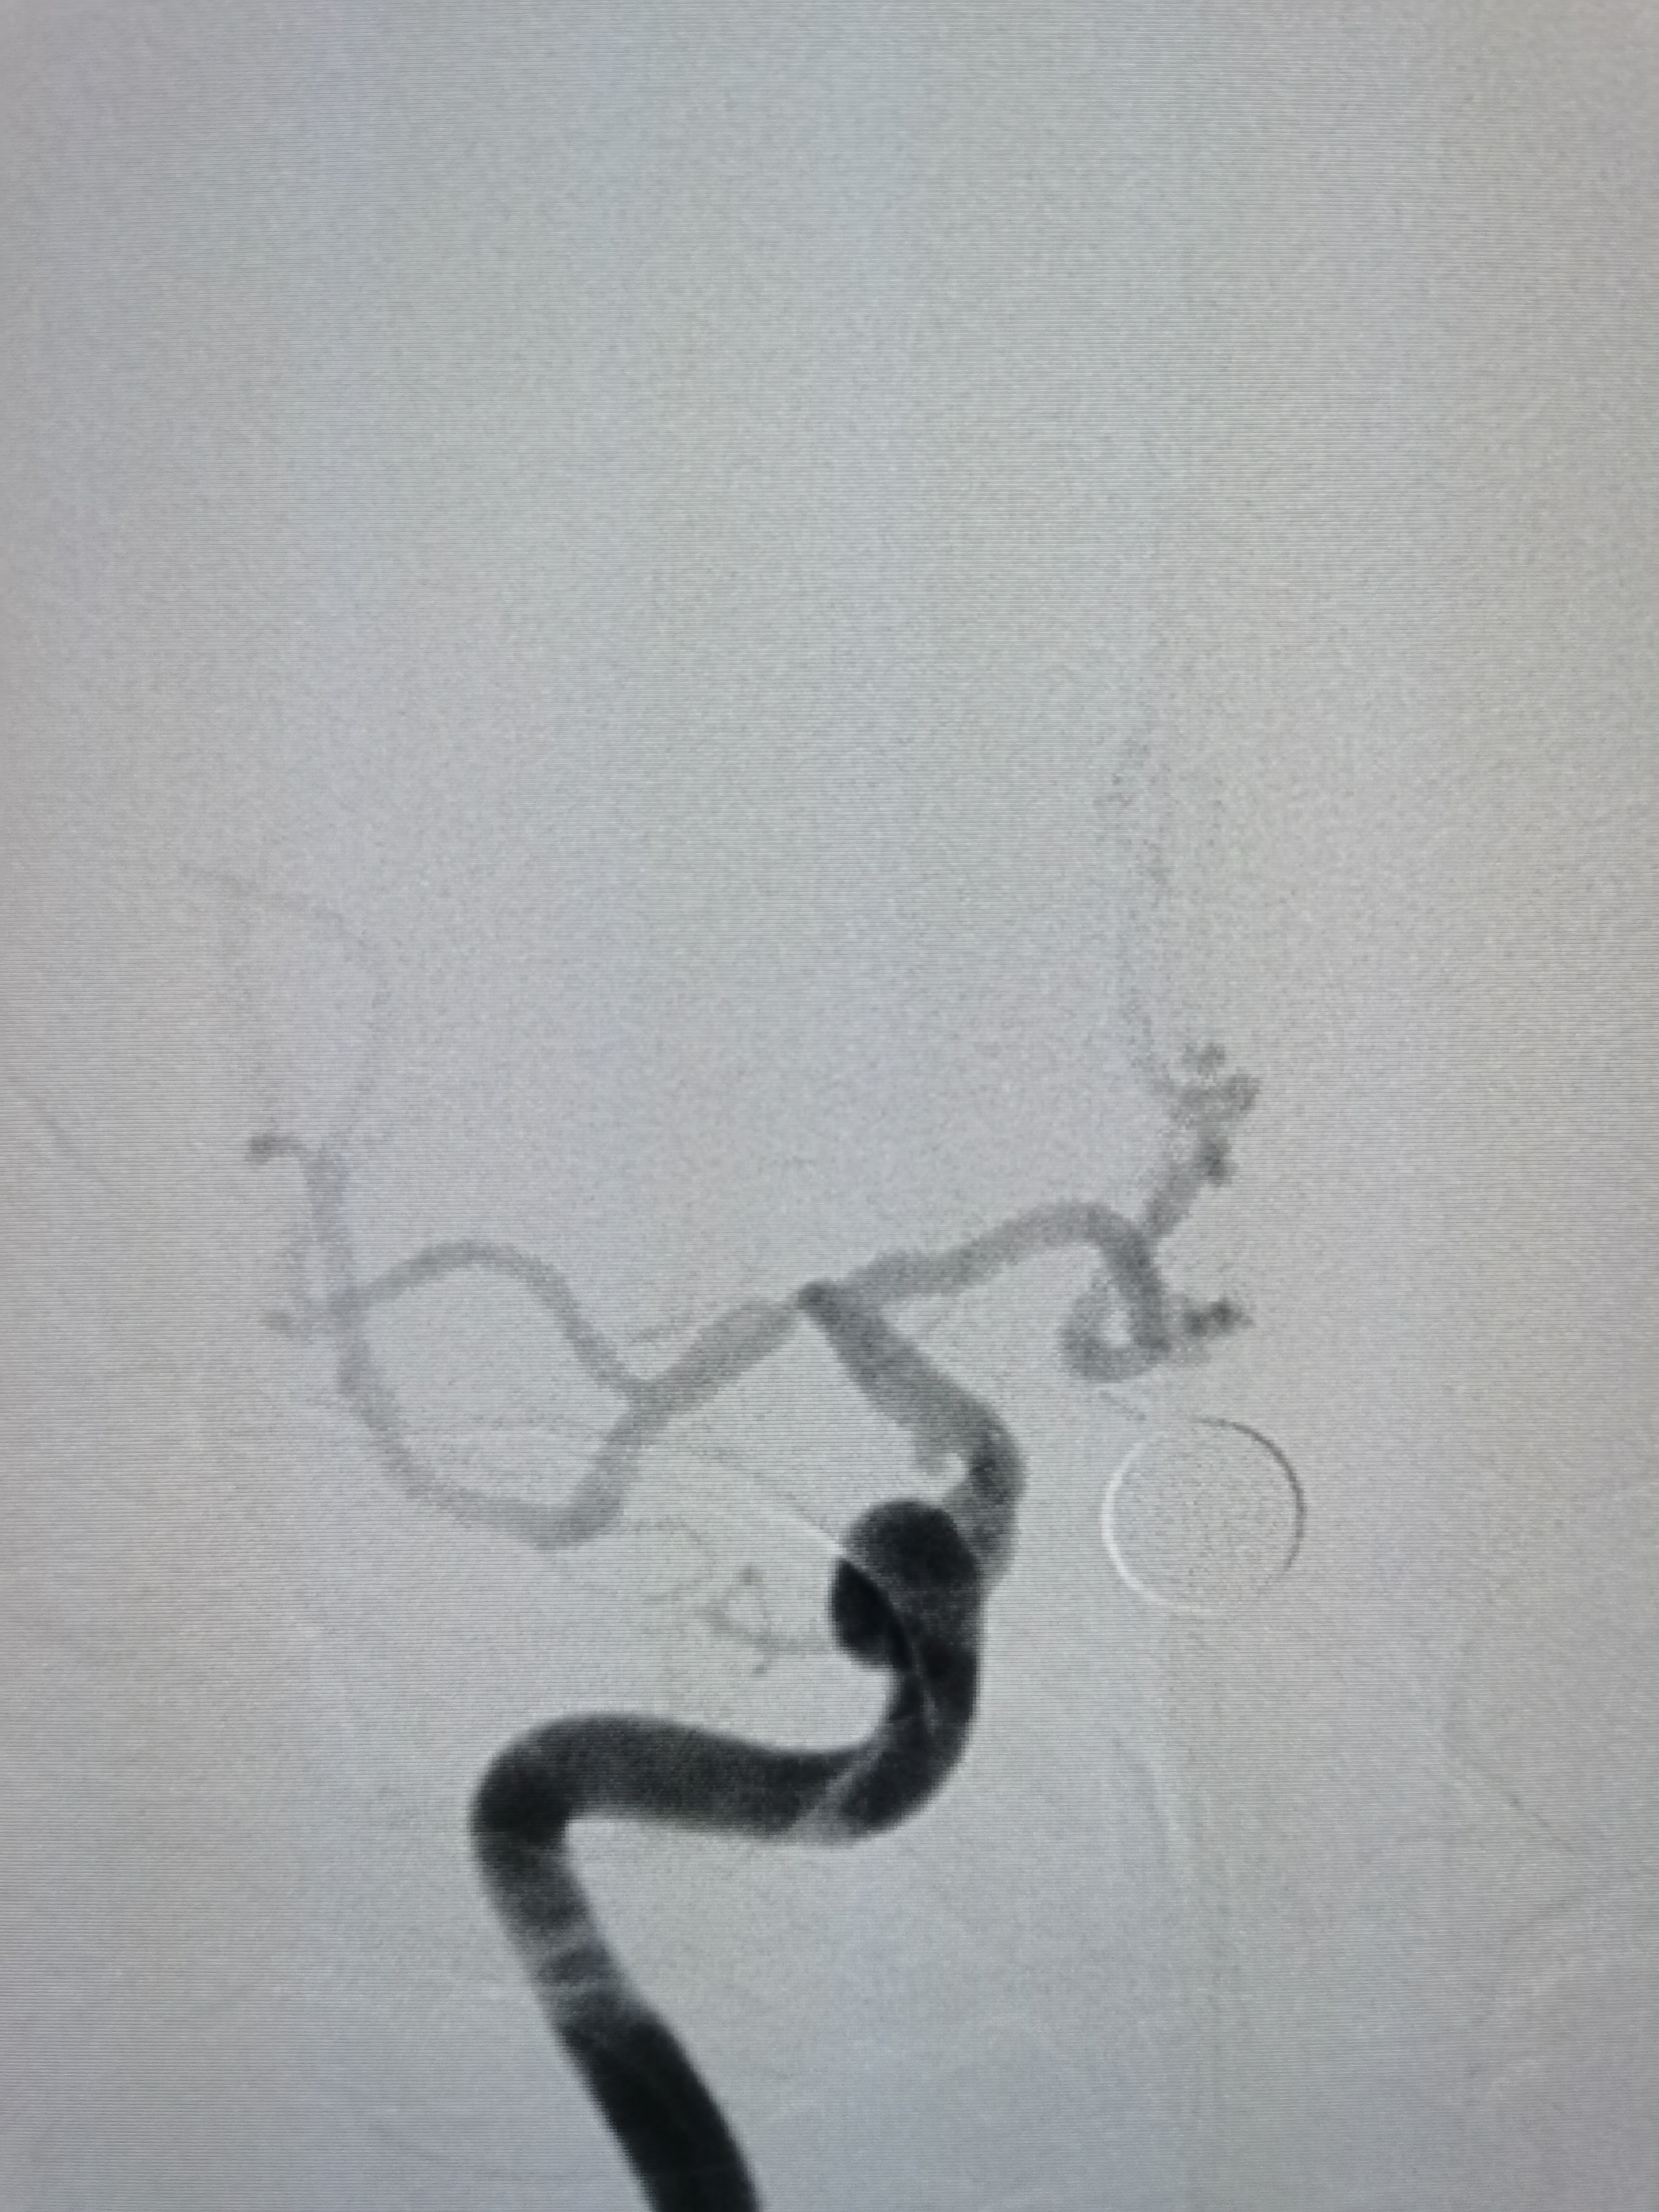

右侧颈内动脉起始部粥样硬化斑块形成。

颅内侧位显影可。

右侧大脑中动脉M1段重度狭窄。

右侧大脑中动脉M1段重度狭窄,病变处存在豆纹动脉。